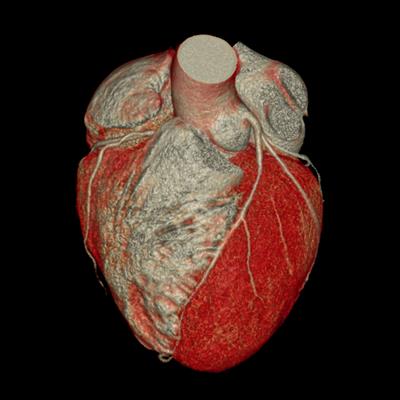

Challenges in the Contemporary Assessment of Coronary Physiology

- Dejan Orlic

- Milorad Tesic